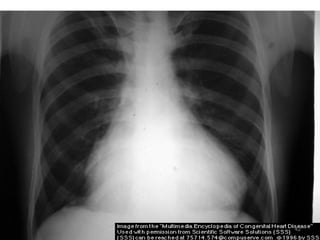

 CXR - Right. V & A enlargement

- Large pulm. artery

- ↑ed pulm. vascularity

 ECG - volume overload,

- right axis deviation

- minor right ventricular conduction delay

 Echocardiography

 Catheterization